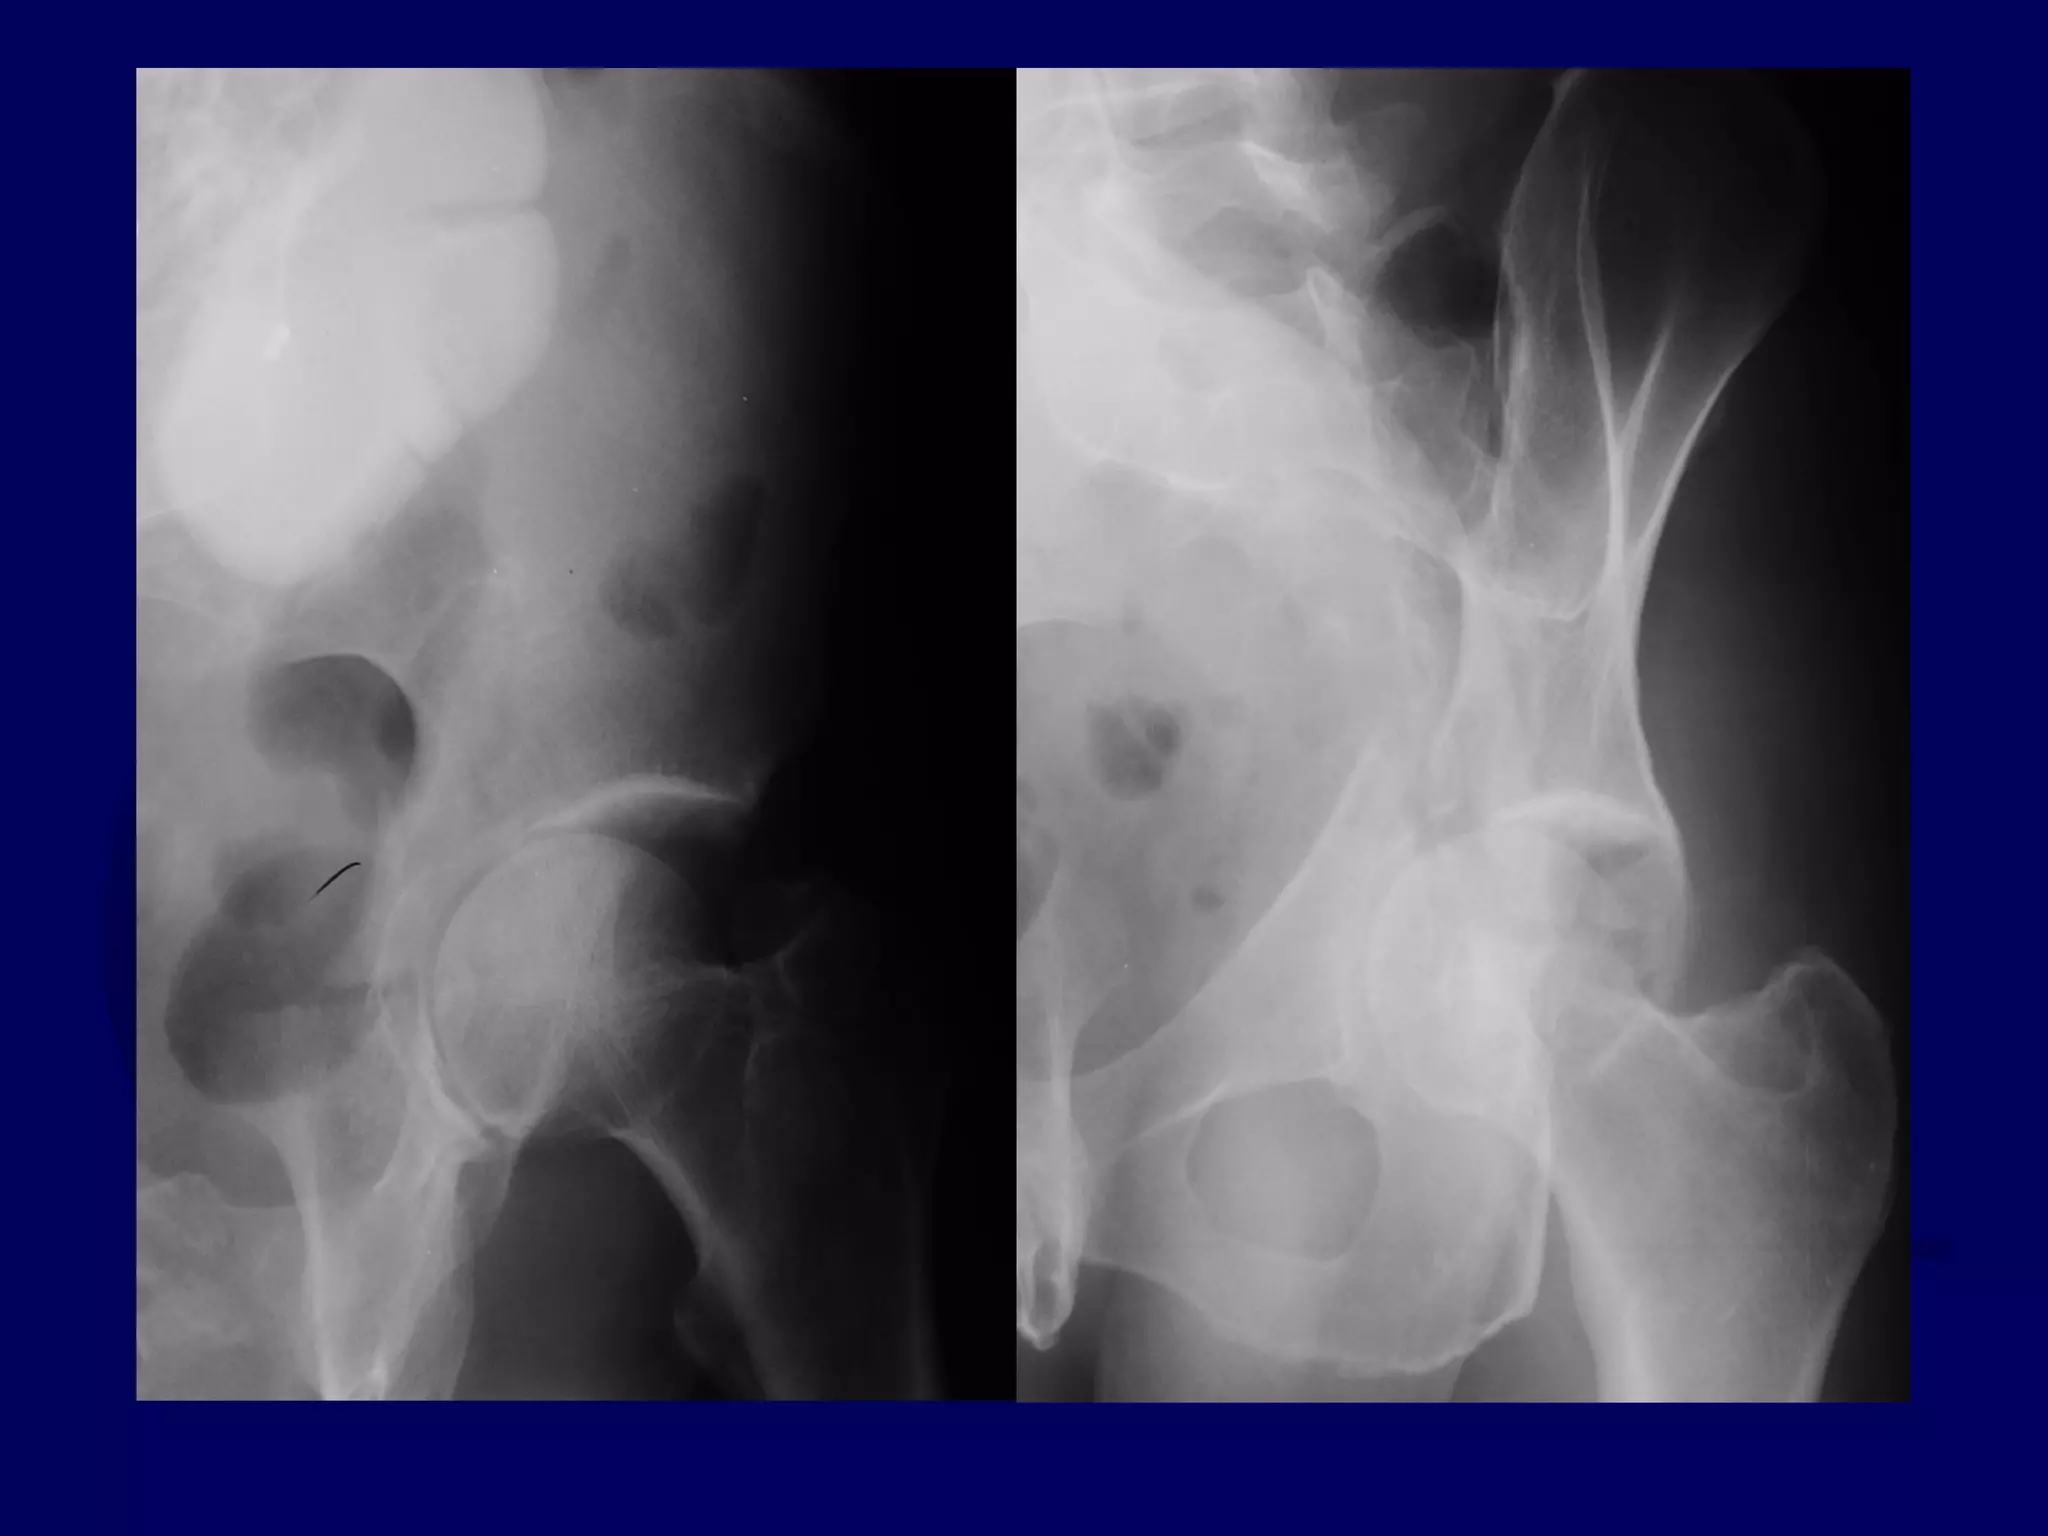

Both Column

Acetabular Fracture

18 Y.O. Female

Isolated Injury

R.C. 00.03.09

SPUR

SIGN

Completion of Iliac Fracture

Reduction of Anterior Column

to Intact Ilium

Reduction of Posterior Column

INTACT ILIUM

R.C. 00.03.10